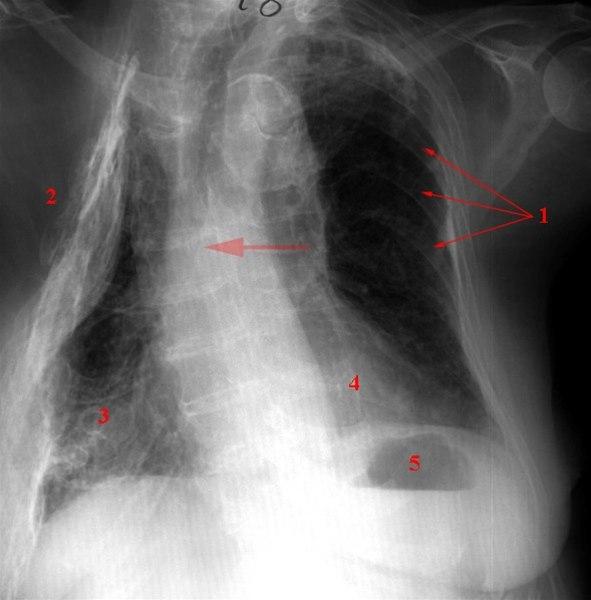

Forandringer etter torakoplastikk på høyre side

- Ribben

- Sammenfall etter torakoplastikk (fjerning av costae). Den friske siden forskyvd over mot den syke

- Fortetninger i høyre underlapp

- Hjerteskyggen

- Luft under v. diafragmakuppel, normalfenomen